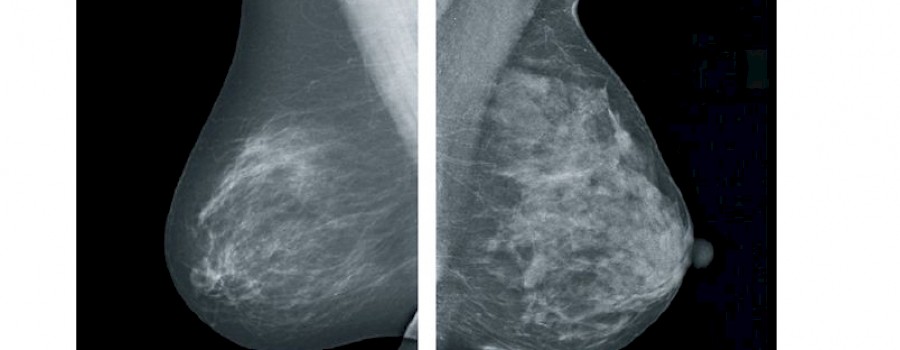

Die KBV (Kassenärztlichen Bundesvereinigung) hat auf der Grundlage der Qualitätsprüfungen bundesweite statistische Analysen durchgeführt, in die über 79.000 Mammographie-Aufnahmen aus etwa 20.000 Untersuchungen (Patientinnen) eingingen.